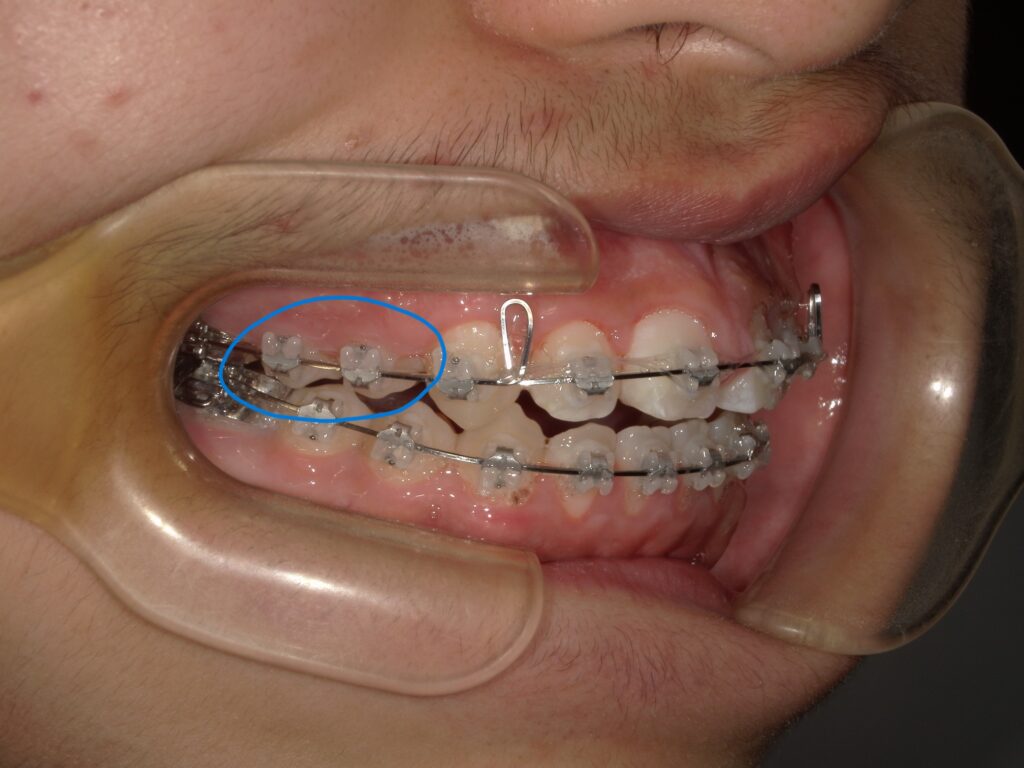

ワイヤー矯正やブラケット矯正の場合、歯に装置がついていることで食べかすやプラーク(歯垢)が残りやすくなります。特に複雑な装置のまわりは歯ブラシが届きにくく、子どもだけの歯みがきでは取り切れないことが多いです。

歯ぐきの腫れが進行すると、写真のように歯ぐきがブラケット装置を覆ってしまうことも。こうなると、繰り返し装置の脱離や、歯に装置が付けられないことから治療が進まなくなることがあります。